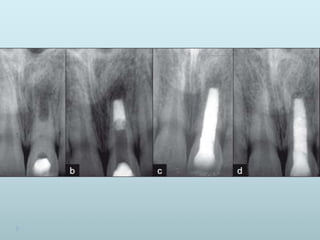

Recall patient in 3 months to determine

whether a calcific barrier has developed

at or near root apex (radiographically)

If not a fresh supply of calcium hydroxide

is applied into root canal and patient recall

every 3 months until one sees

radiographic evidence of apical barrier

Root canal obturated after completion of

apexification